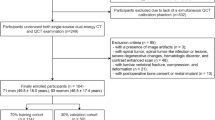

This retrospective study was approved by the institutional review board of the National Cheng Kung University Hospital (NCKUH). Female patients who were diagnosed with breast cancer and received a complete course of treatment and follow-up between 2011 and 2021 were initially selected. Inclusion criteria were: (i) patients who underwent post-treatment thoracic CT scan and had unenhanced CT images that showed L1 vertebra; (ii) patients who underwent post-treatment DXA scan of the lumbar spine (L1 to L4 vertebrae) and (iii) the time interval between CT scan and DXA scan was less than 1 year. Exclusion criteria were: (i) patients with lumbar scoliosis, lumbar compression fractures, or radiodense osteophytosis in the lumbar vertebrae and (ii) patients with a history of lumbar surgery.

Subsequently, 8 out of 449 radiomic features with optimal lambda values were selected by the least absolute shrinkage and selection operator (LASSO) regression analysis (Supplementary Table S2). However, because of high correlation with each other, two radiomic features were further excluded. As a result, only 6 radiomic features were retained for the final statistical analysis (Supplementary Table S2). Data processing and analysis for the present study is shown in Fig. 1.

A total of 412 breast cancer patients receiving post-treatment DXA examination and thoracic CT scan were included in the study. Clinical data and CT-based radiomic features were collected from all 412 patients.